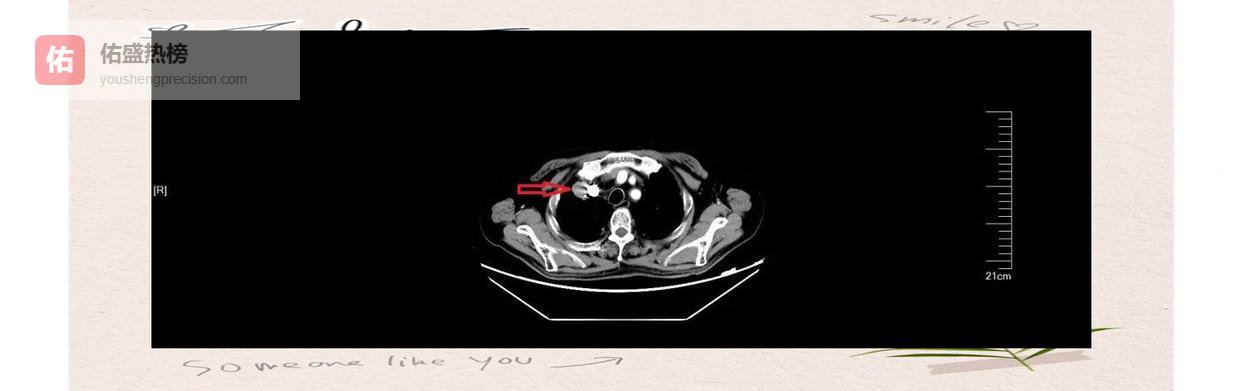

2.3 ► 术后即刻“验收” 植入后立刻行SPECT/CT显像,医生可直观看到粒子分布密度与覆盖范围,当场评估是否需要补种。

术后随访:出院前再次行SPECT/CT,确认粒子位置与剂量释放曲线,确保“种子”在位、剂量达标、范围安全。